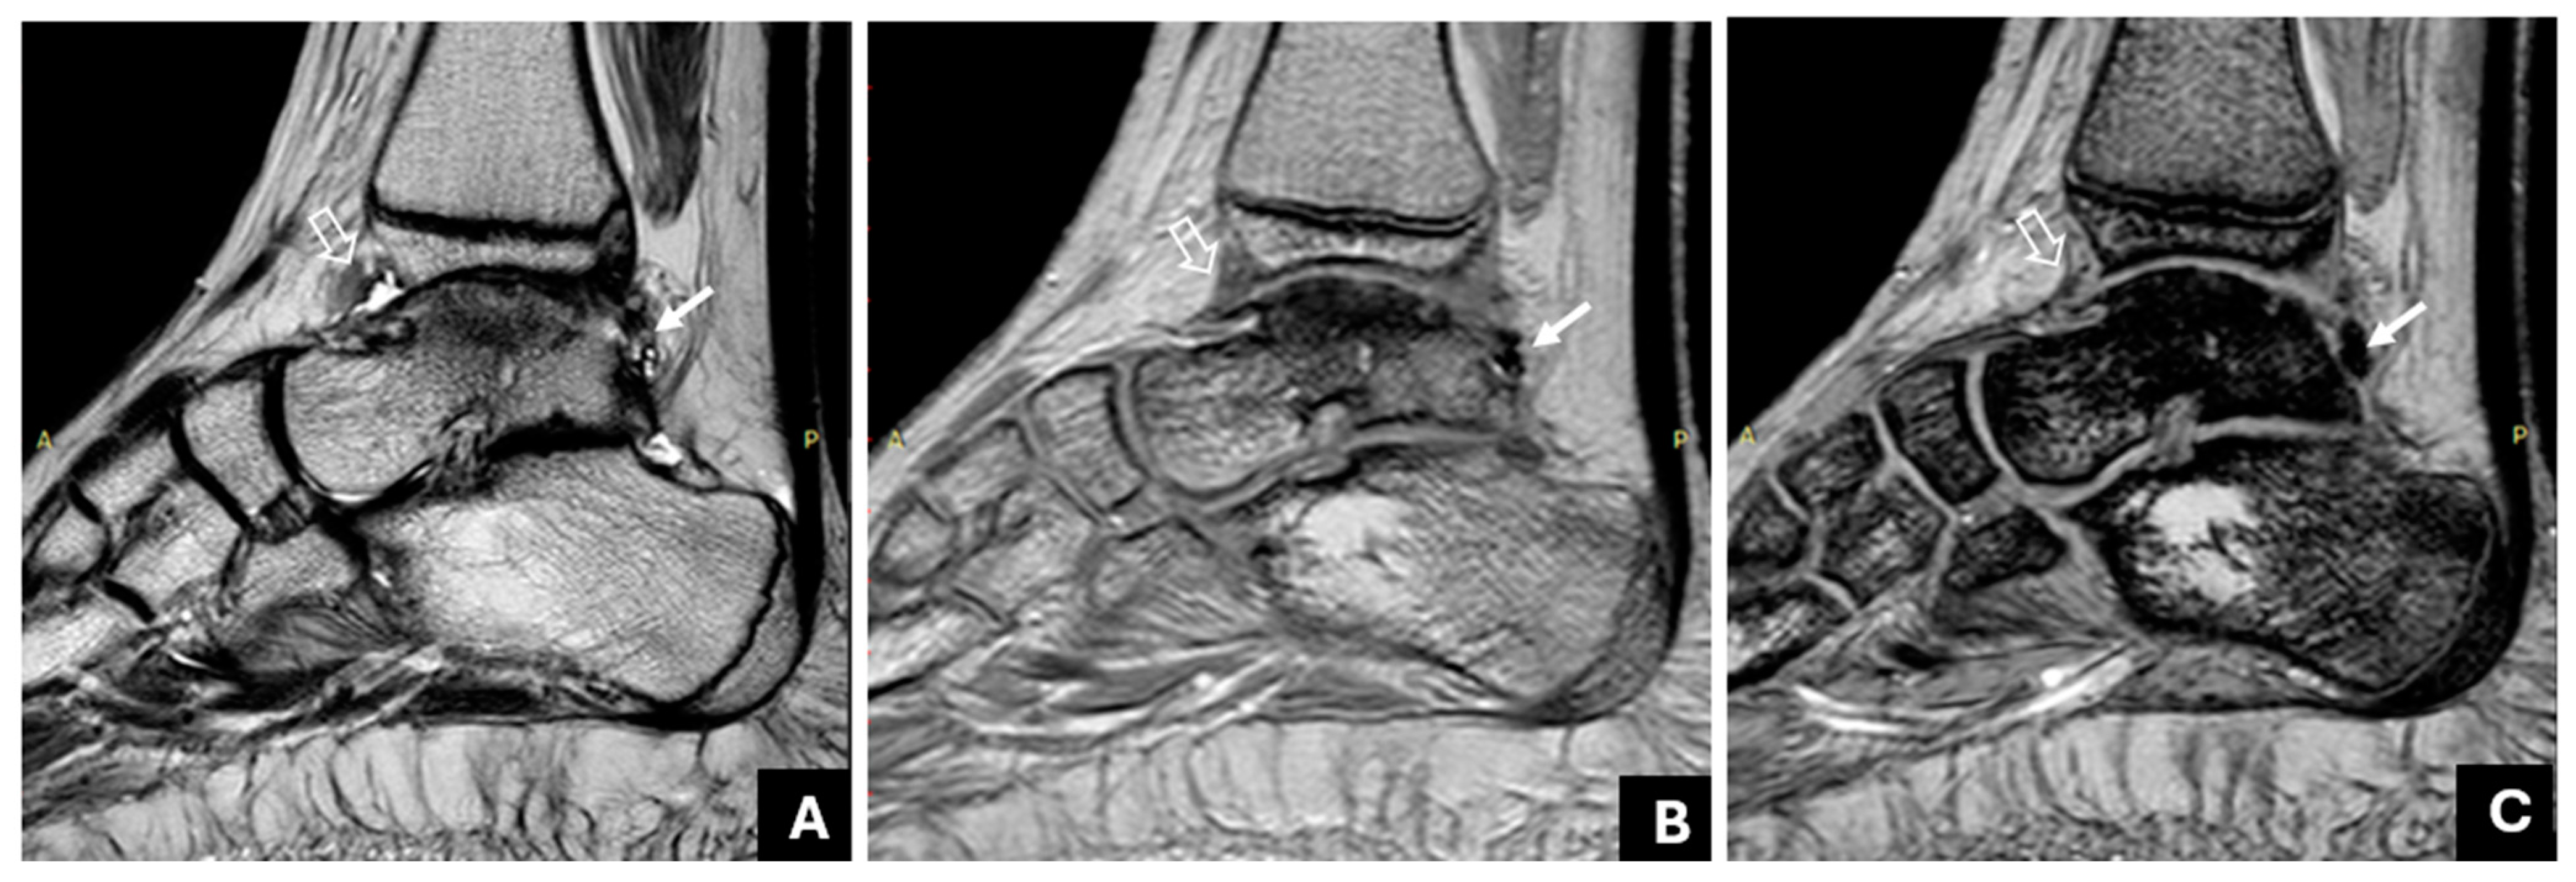

3.1. Detection of Joint Hemosiderin Deposition with mGRE Sequence: Inter-Reader Agreement

3.2. The Association of Joint Hemosiderin Deposition with Synovial Thickening, Effusion, and Osteochondral Changes (OCC)